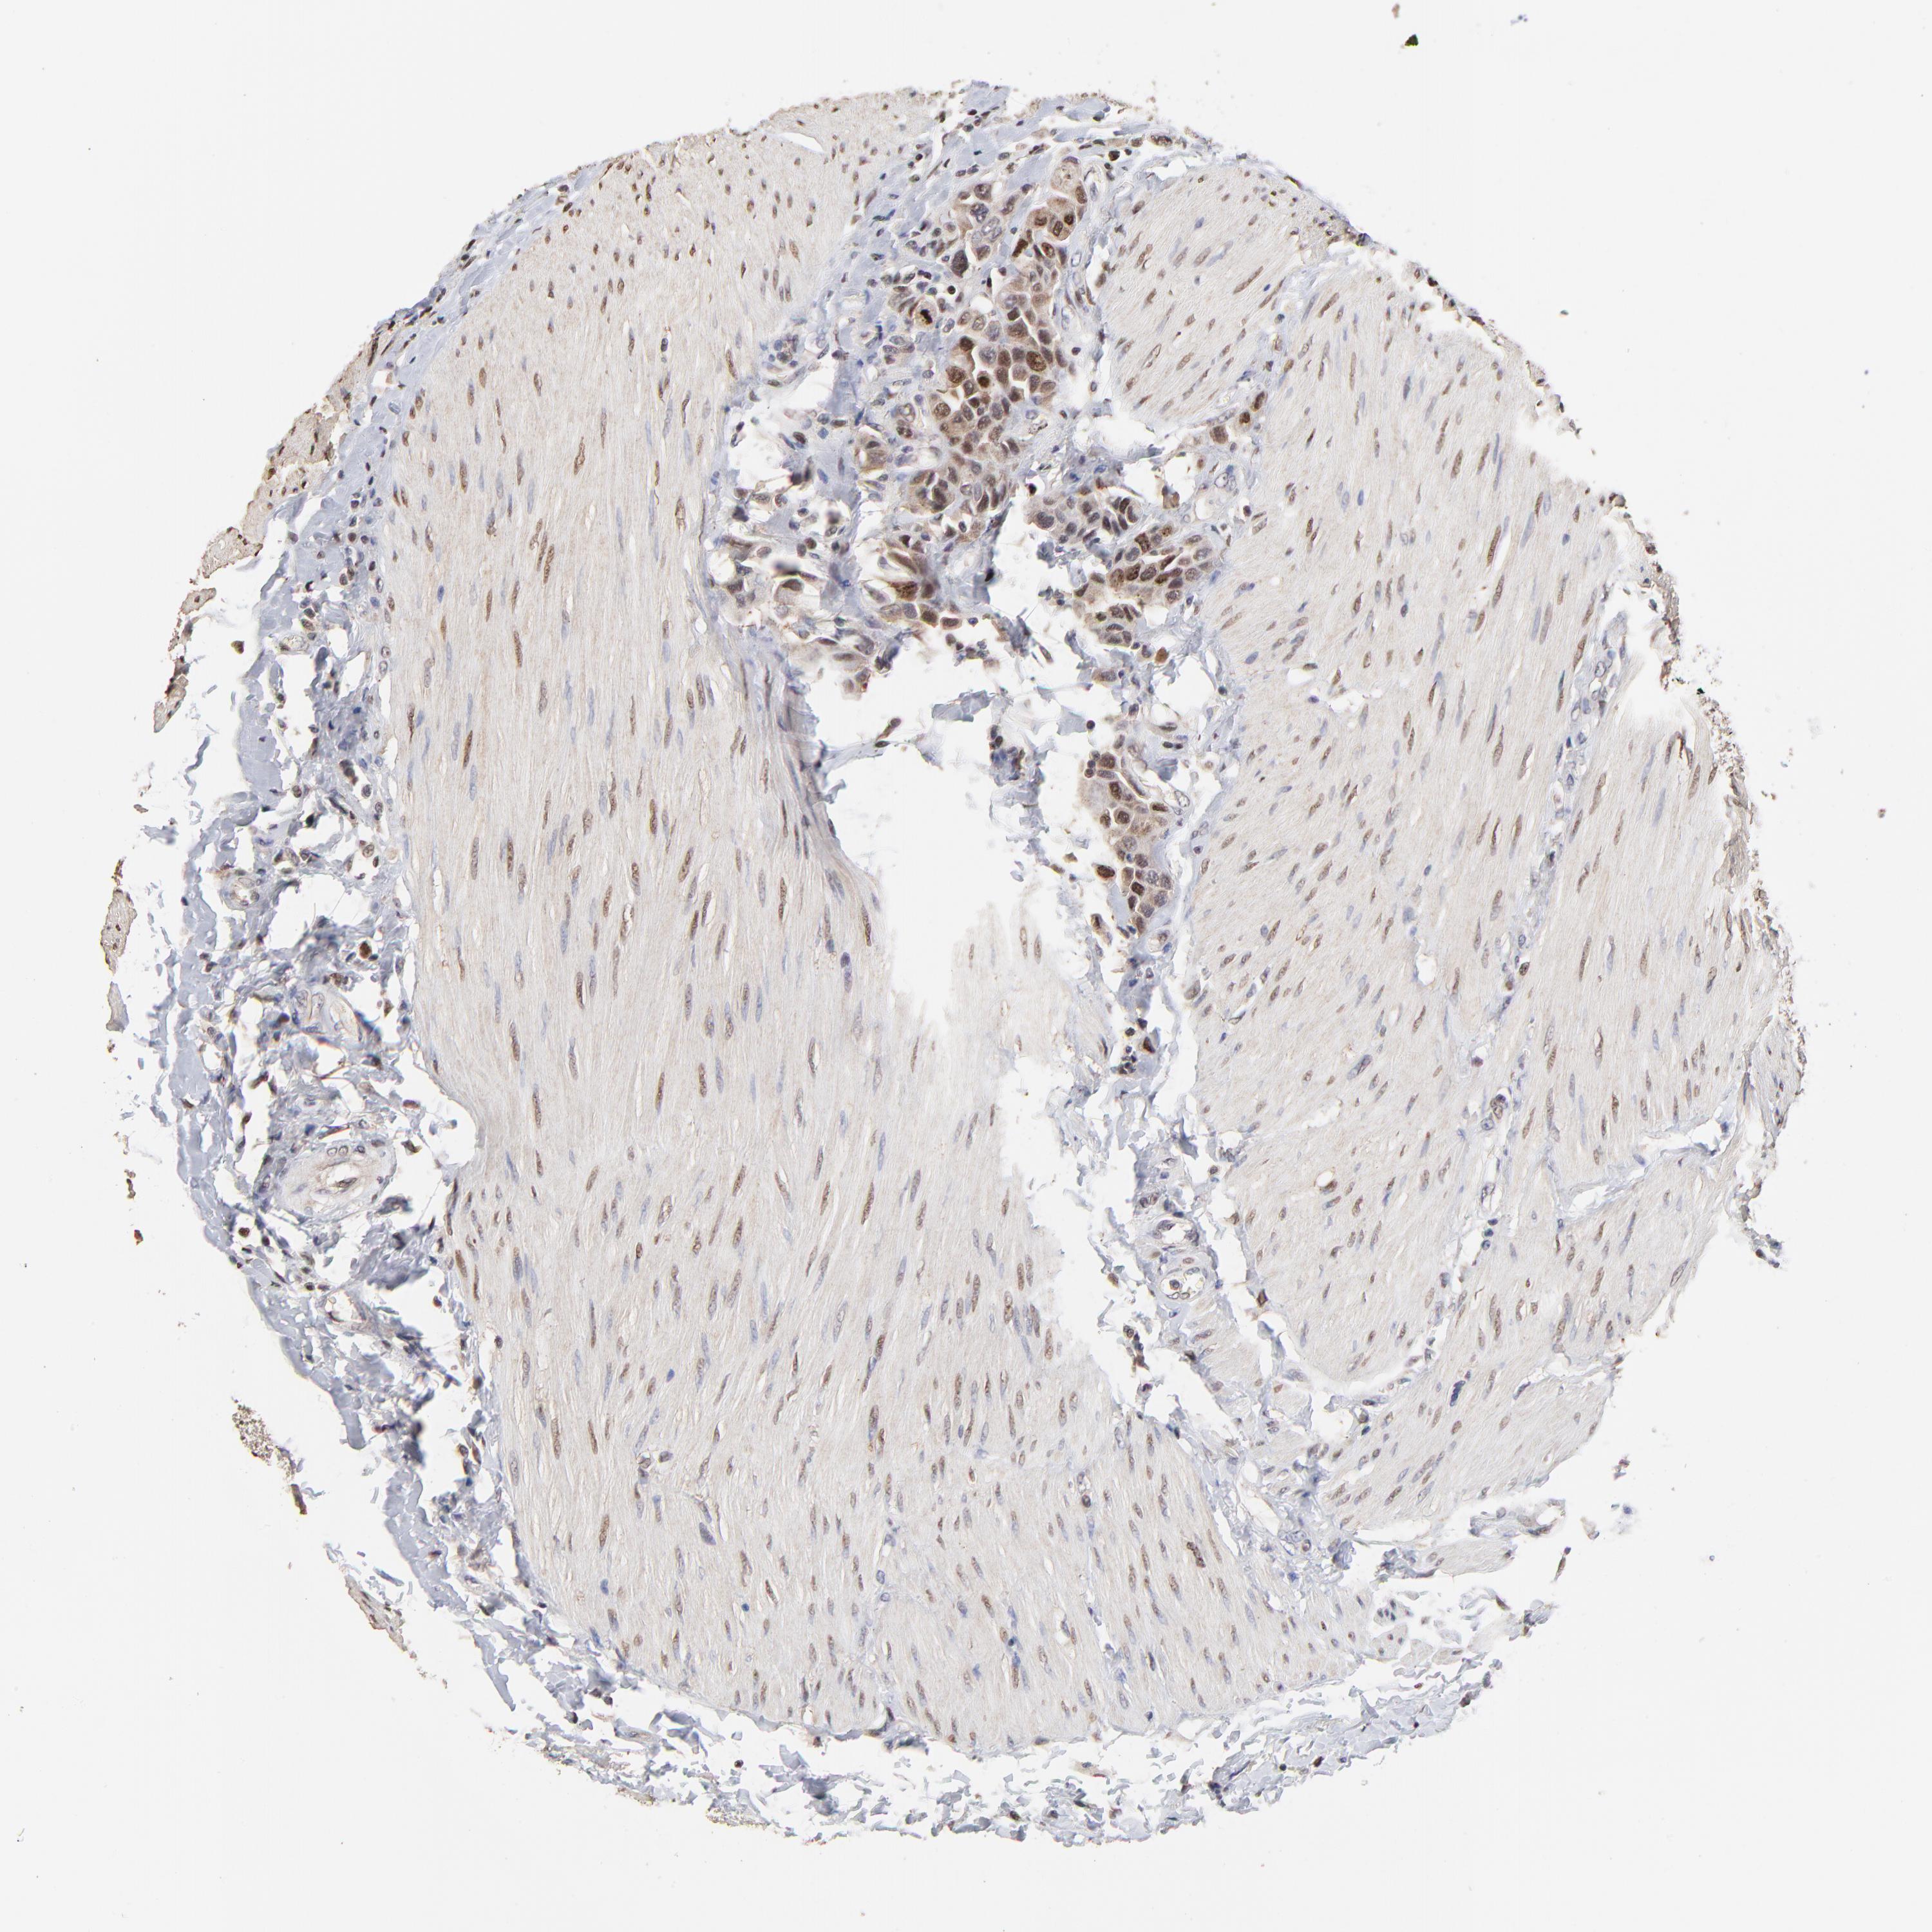

UROTHELIAL CANCER - Protein expressioni

A mouse-over function shows sample information and annotation data. Click on an image to view it in a full screen mode. Samples can be filtered based on level of antibody staining by selecting one or several of the following categories: high, medium, low and not detected. The assay and annotation is described here.

Antibody stainingi

Antibody staining in the annotated cell types in the current human tissue is reported as not detected, low, medium, or high, based on conventional immunohistochemistry profiling in selected tissues. This score is based on the combination of the staining intensity and fraction of stained cells.

Each image is clickable and will lead to virtual microscopy that enables deeper exploration of all samples and also displays staining intensity scores, fraction scores and subcellular localization as well as patient and tissue information for each sample.

Antibody HPA002830

Antibody CAB004270

Staining

High

Medium

Low

Not detected

Intensity

Strong

Moderate

Weak

Negative

Quantity

>75%

75%-25%

<25%

None

Location

Nuclear

Cytoplasmic/membranous

Cytoplasmic/membranous,nuclear

Urothelial carcinoma, High grade

Urothelial carcinoma, Low grade